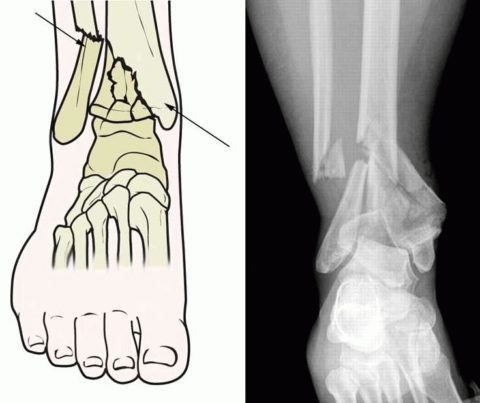

Фото: как выглядит нарушенная целостность кости

Рентгенологический снимок полученной травмы